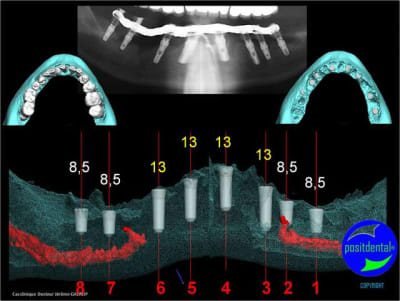

gestion des artéfacts en présence de couronnes

et la projet 10 implants maxillaire sup

10 en haut

donc ce sera minimum 8 en fonction du scan